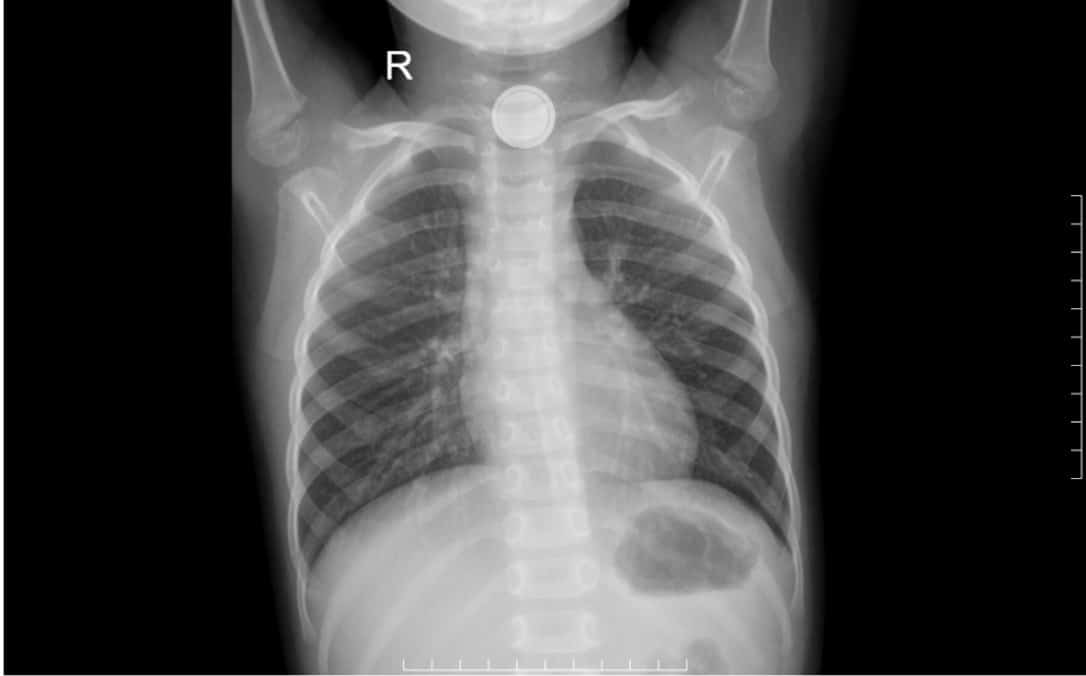

Bé gái 4 tuổi thoát thủng thực quản do nuốt pin cúc áo: Cha mẹ cần lưu ý gì?

Pin cúc áo tưởng chừng vô hại khi cầm trên tay, nhưng việc vô tình nuốt pin có thể gây thủng thực quản do khả năng ăn mòn mạnh. Pin cúc áo ở thực quản…